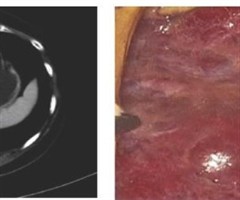

射频消融, “一根针” 能治疗肝癌吗?

想象一下:一根比牙签还细的探针,在影像技术的精确引导下,穿刺进入人体最重要的代谢“化工厂”一肝脏,直达肝脏内的肿瘤内部。随后,探针释放出可控的高频电流,产生足以灭活癌细胞的高温。这并非科幻情节,而是现代医学对抗肝癌的尖兵利器一射频消融治疗(...